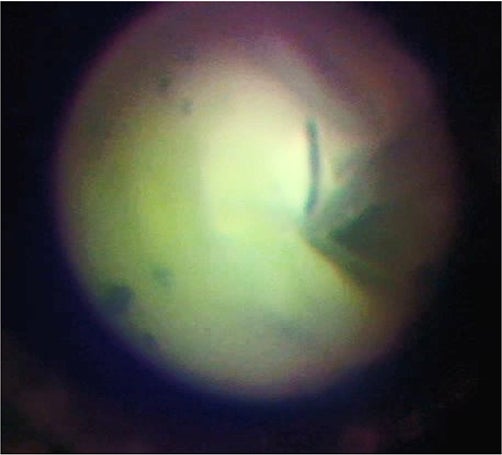

突発性難聴、顔面神経麻痺、外リンパ瘻といった疾患患者は本邦内で推計13.5万人にのぼる。これらの疾患においては、内耳や顔面神経の異常が原因となる。標準的な治療として内耳や神経の治療を目的とした全身ステロイド投与が行われる。効果がない場合には、鼓膜を小切開し、細径の内視鏡で病変部位(患部)を確認の上、薬剤を内耳や顔面神経に直接投与することで効果的な治療が期待される。

これまで既存の内視鏡を用いて同治療方法を試みたが、画像解像度の高い大径内視鏡では鼓膜切開が大きくなり、術後に鼓膜穿孔をきたすリスクがある。また、既存の極細径内視鏡を使用した場合には、画像解像度が低く、患部の確認が困難であった。Cellendo Scopeは細径と高解像度を兼ね備えており、当治療における患部観察に最適である。本年度の研究では、Cellendo Scopeを用い患部観察、薬剤投与を行い、薬効までの評価を目指す。

図6:鼓膜周辺模型のGI-POF極細内視鏡観察。左)外耳道からの内視鏡挿入、中)鼓膜小孔切開、右)鼓膜内観察